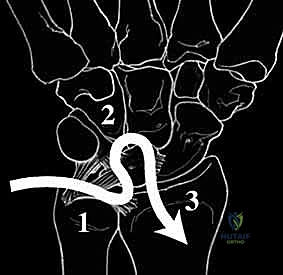

The lunotriquetral interosseous ligament, much like the scapholunate ligament, is a C-shaped structure. It spans the dorsal, proximal, and palmar edges of the articulation between the lunate and the triquetrum.

- Palmar Portion: This is the thickest and biomechanically most crucial region of the entire LT complex. It plays a primary role in transmitting the extension moment of the triquetrum as it engages the hamate. Injury here significantly compromises stability.

- Dorsal Portion: While not as robust as the palmar component, the dorsal lunotriquetral ligament is vital as a rotational constraint. Its integrity is essential for preventing abnormal rotation between the lunate and triquetrum.

- Membranous Region: This central, more delicate part has minimal effect on rotation, translation, or distraction, primarily serving as a synovial barrier.

The lunate, fellows, is often described as a "balanced lunate" – it's torque-suspended between the scaphoid and the triquetrum. The scaphoid inherently tends to palmar flex, while the triquetrum tends to extend. The scapholunate and lunotriquetral ligaments act as critical tethers, balancing these opposing forces and ensuring the entire proximal carpal row moves in a coordinated fashion about the lunate.

When the lunotriquetral ligament complex is disrupted, this delicate balance is lost. Injuries can range from partial tears with dynamic dysfunction – which is the most common presentation – to complete dissociation with static collapse.

- Lunotriquetral Dissociation: This refers to a complete rupture of both the dorsal and palmar regions of the lunotriquetral ligament.

- Volar Intercalated Segment Instability (VISI): This is a more severe form of carpal collapse. While LT dissociation is a prerequisite, VISI requires additional compromise of secondary restraints, most notably the dorsal radiotriquetral ligament. Without the integrity of this extrinsic ligament, static carpal instability ensues, characterized by a volar-flexed lunate and an abnormal lunotriquetral angle. On a lateral radiograph, a normal lunotriquetral angle is approximately 14 degrees. In VISI, this angle can increase to -16 degrees or more, indicating volar flexion of the lunate.